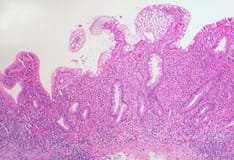

Colonic dysplasia is a precursor to adenocarcinoma and occurs in patients with ulcerative colitis.

Many physicians use surveillance colonoscopy for monitoring patients with ulcerative colitis and determining the need for colectomy. This involves scheduled annual or biannual colonoscopy with multiple random biopsies.

However, surveillance colonoscopy must be undertaken with caution, because even low-grade dysplasia is associated with synchronous adenocarcinoma in as many as 42% of cases, and as many as 84% of neoplasms in persons with ulcerative colitis are missed at random biopsy.

Furthermore, 1% of colon cancers in patients with ulcerative colitis have no foci of preexisting dysplasia. Even in patients in whom the disease is medically controlled, the optimal time for colectomy may be 7-10 years after the onset of disease, to prevent colon cancer. [6]

Historically, patients with ulcerative colitis had a 1% risk of colon adenocarcinoma per year after 8-10 years of disease. After 20 years of disease, the incidence of adenocarcinoma was as high as 25%. [7] However, data acquired after the advent of improved medical therapy suggested that the incidence of adenocarcinoma has decreased somewhat. Among 600 patients colonoscopically examined for 30 years, the cumulative risk of cancer was only 2.5% at 20 years, 7.6% at 30 years, and 10.8% at 40 years. [8]

Backwash ileitis is an independent marker for the presence of dysplasia, as is age older than 45 years and the presence of disease for more than 10 years. Therefore, the patient with ulcerative colitis must be made aware of the significant risk of colon cancer, and surgical intervention in nonacute cases must be encouraged after 10 years of disease.